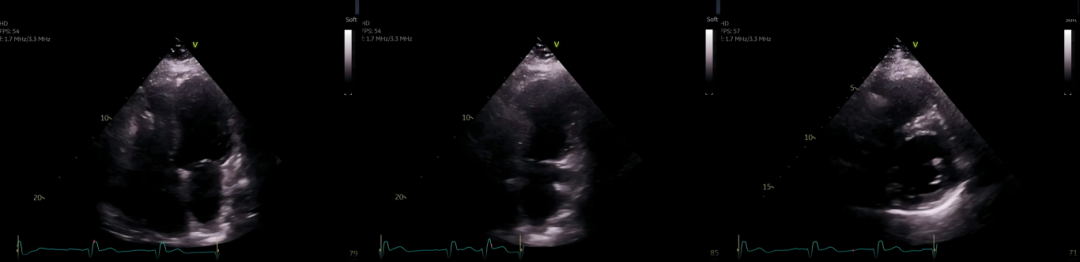

肺部无影的呼吸困难,原因竟然是它!看床旁超声如何破解这场多病共存患者的生死迷局

病史摘要:54 岁男性,因“呼吸困难 1 周”就诊,平卧位或活动时加重,休息缓解,无发热、咳嗽及下肢水肿,体温、生命体征平稳。既往有哮喘、高血压、糖尿病及终末期肾病血液透析病史。 诊疗过程:查体双肺呼吸音清,心脏听诊因体型受限。床旁肺部超声未见肺水肿或胸腔积液,床旁心脏超声显示连枷样主动脉瓣伴活动性高回声团块致主动脉瓣关闭不全,经食管超声心动图进一步证实,确诊为感染性心内膜炎导致连枷样主动